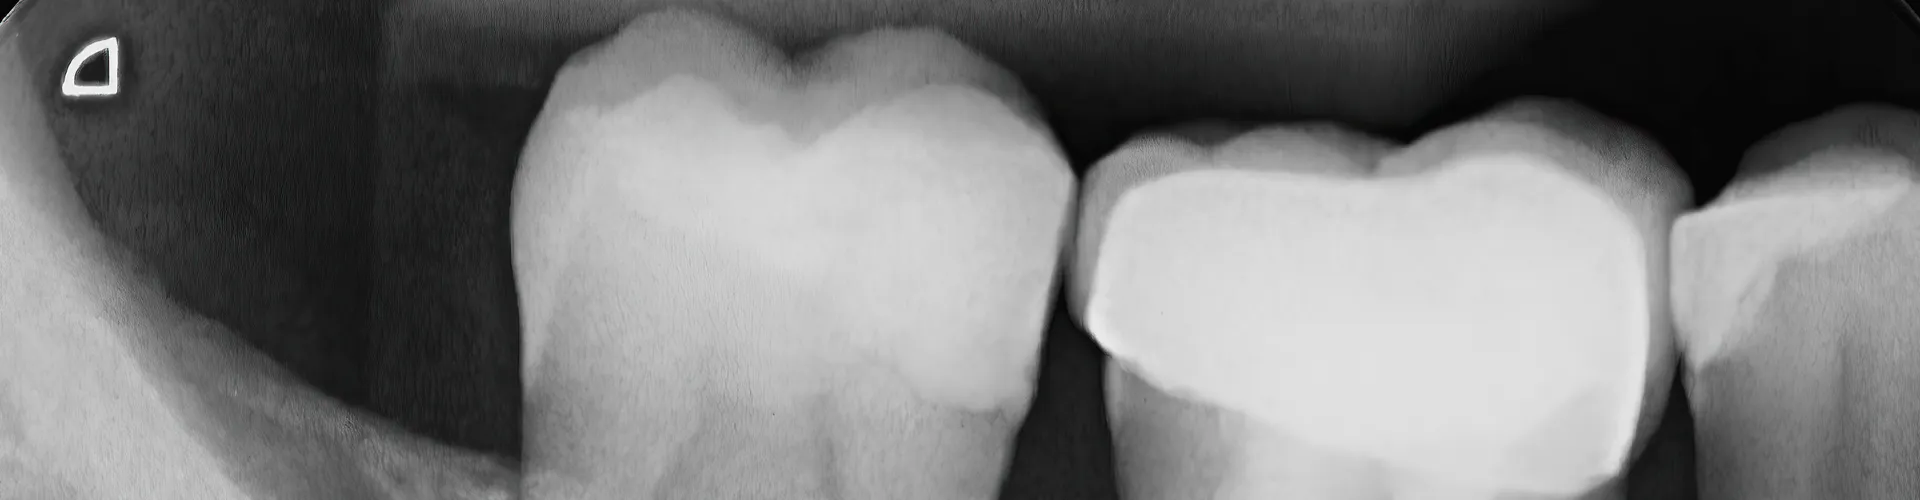

An endodontist uses 3D imaging techniques and radiographs to capture detailed images of the tiny tooth anatomy. Imaging technologies enable them to better visualize the root canal and other surrounding structures.

The root canal spaces are too small to see clearly with the naked eye. Therefore, endodontists use operating microscopes to view the small anatomical structures and operate effectively.